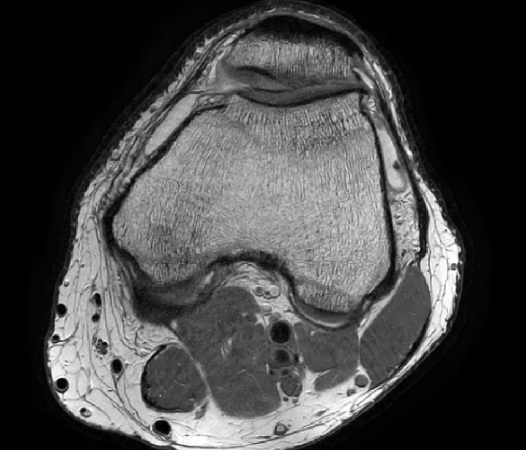

Philips Compressed SENSE

The Compressed SENSE reconstruction then uses iterative, knowledge-based algorithms to fill in the empty lines in k-space (bottom left). This removes the artifacts while keeping the final image fully consistent with the acquired data (bottom right). *Compared to Philips MR exams without Compressed SENSE